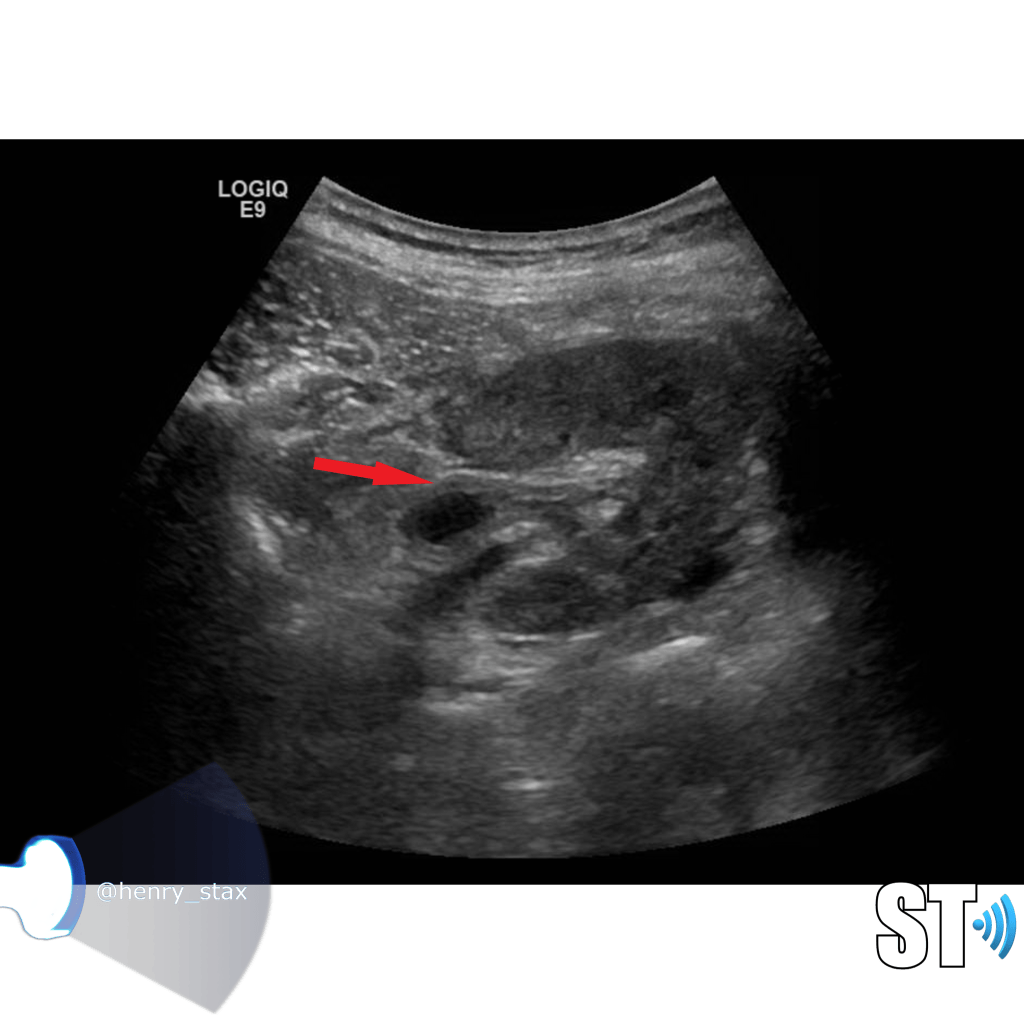

Acute pyelonephritis

Bacterial inflammatory disease of the kidney is commonly cause Eschericia coli. Most infections begin as UTI that ascends to the upper genitourinary system. the infection spreads from the renal pyramids into the renal cortex. The infection may be focal or diffuse. This condition usually presents with chills, fever, flank pain and laboratory findings of urinary infection.

Ultrasound may show an enlarged kidney with edema and increased echogenicity. You may also see a focal triangular area of altered echogenicity that displays reduced perfusion with color Doppler and power Doppler. If left untreated or inadequately treated that area can turn into an abscess.

An abscess will be well formed and distinct from the remainder of the renal parenchyma, it will be heterogeneous, complex appearance with mixed echoic and anechoic portions and no color doppler signal internally..

Once an abscess has formed drainage under ultrasound guidance can be performed. On subsequent imaging you notice some cortical thinning where the abscess was representing scarring.